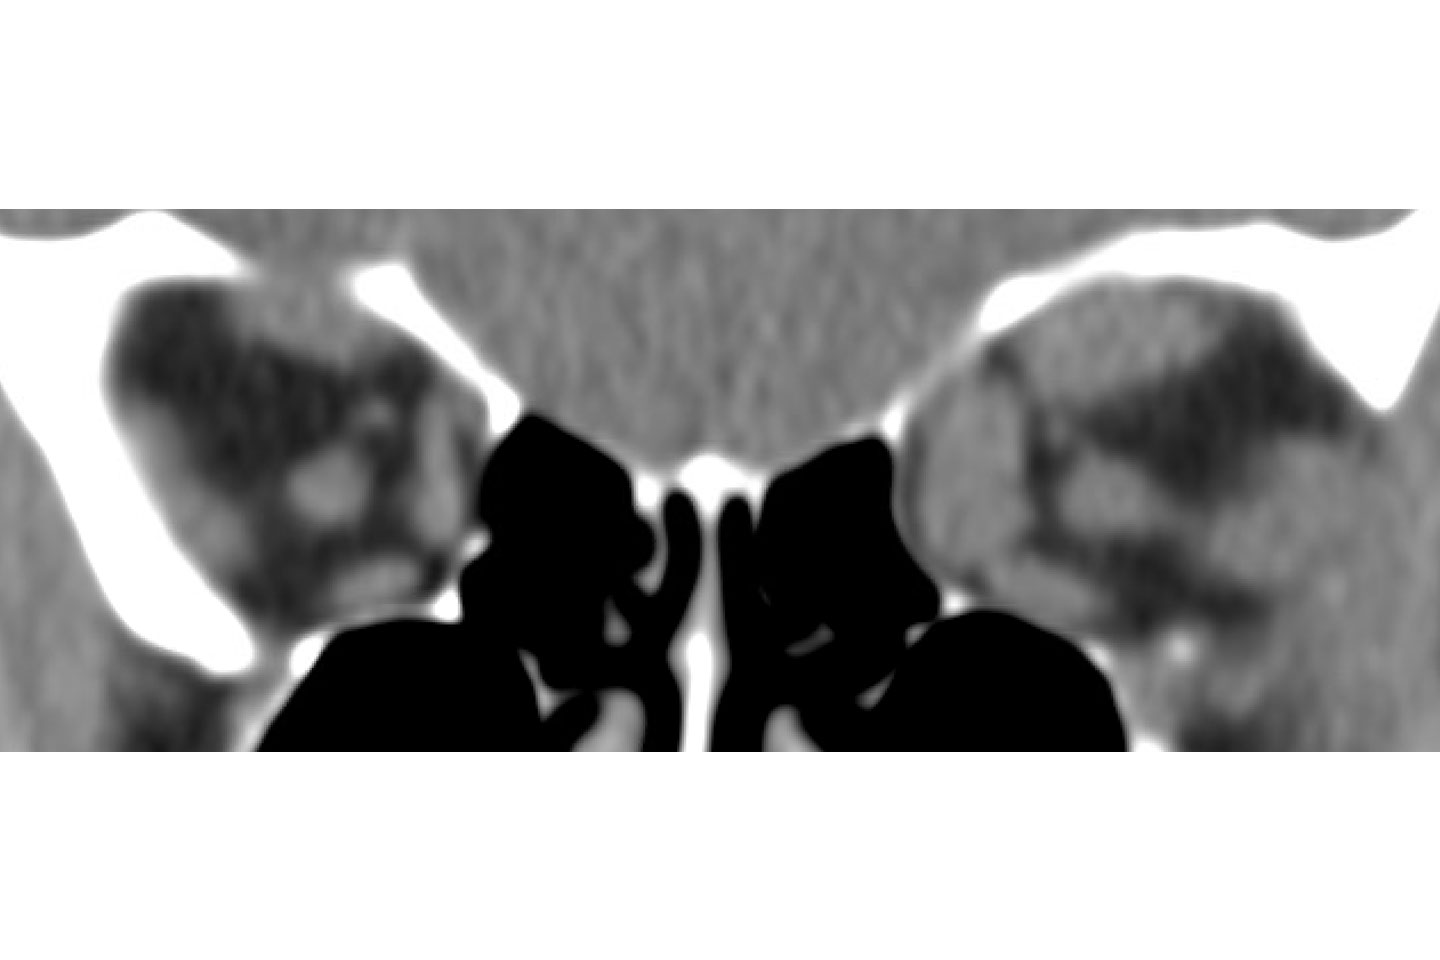

Axial postoperative imaging showing resolution of left exophthalmos. Source: NYU Langone Health